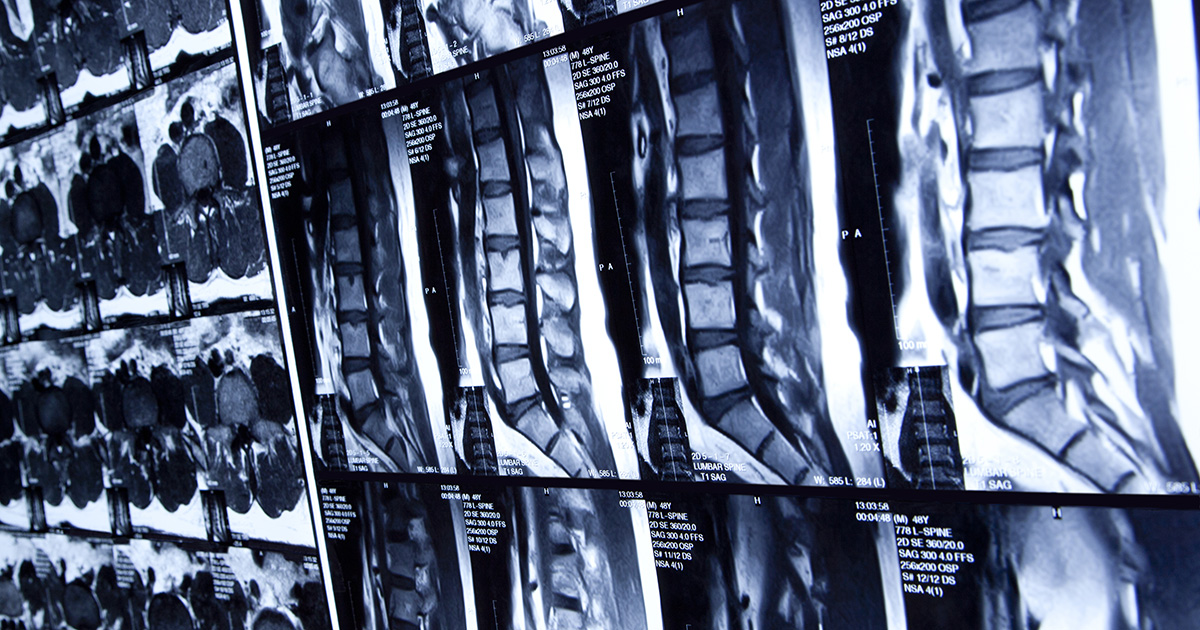

X-rays of lumbar spines

In a paper published in JOR Spine, an open access journal of the Orthopaedic Research Society, researchers looked at patients with and without lumbar degenerative spondylolisthesis to examine the differences in gut microbiome in the two groups.

In a National Institutes of Health-funded study, the researchers collected disc samples from surgery and imaging, along with blood, stool and saliva samples in those without and those with lumbar degenerative spondylolisthesis. This often common condiinvolves slippage of one vertebral body over another due to intervertebral disc or facet joint degeneration — and can lead to pain, disability and surgery.